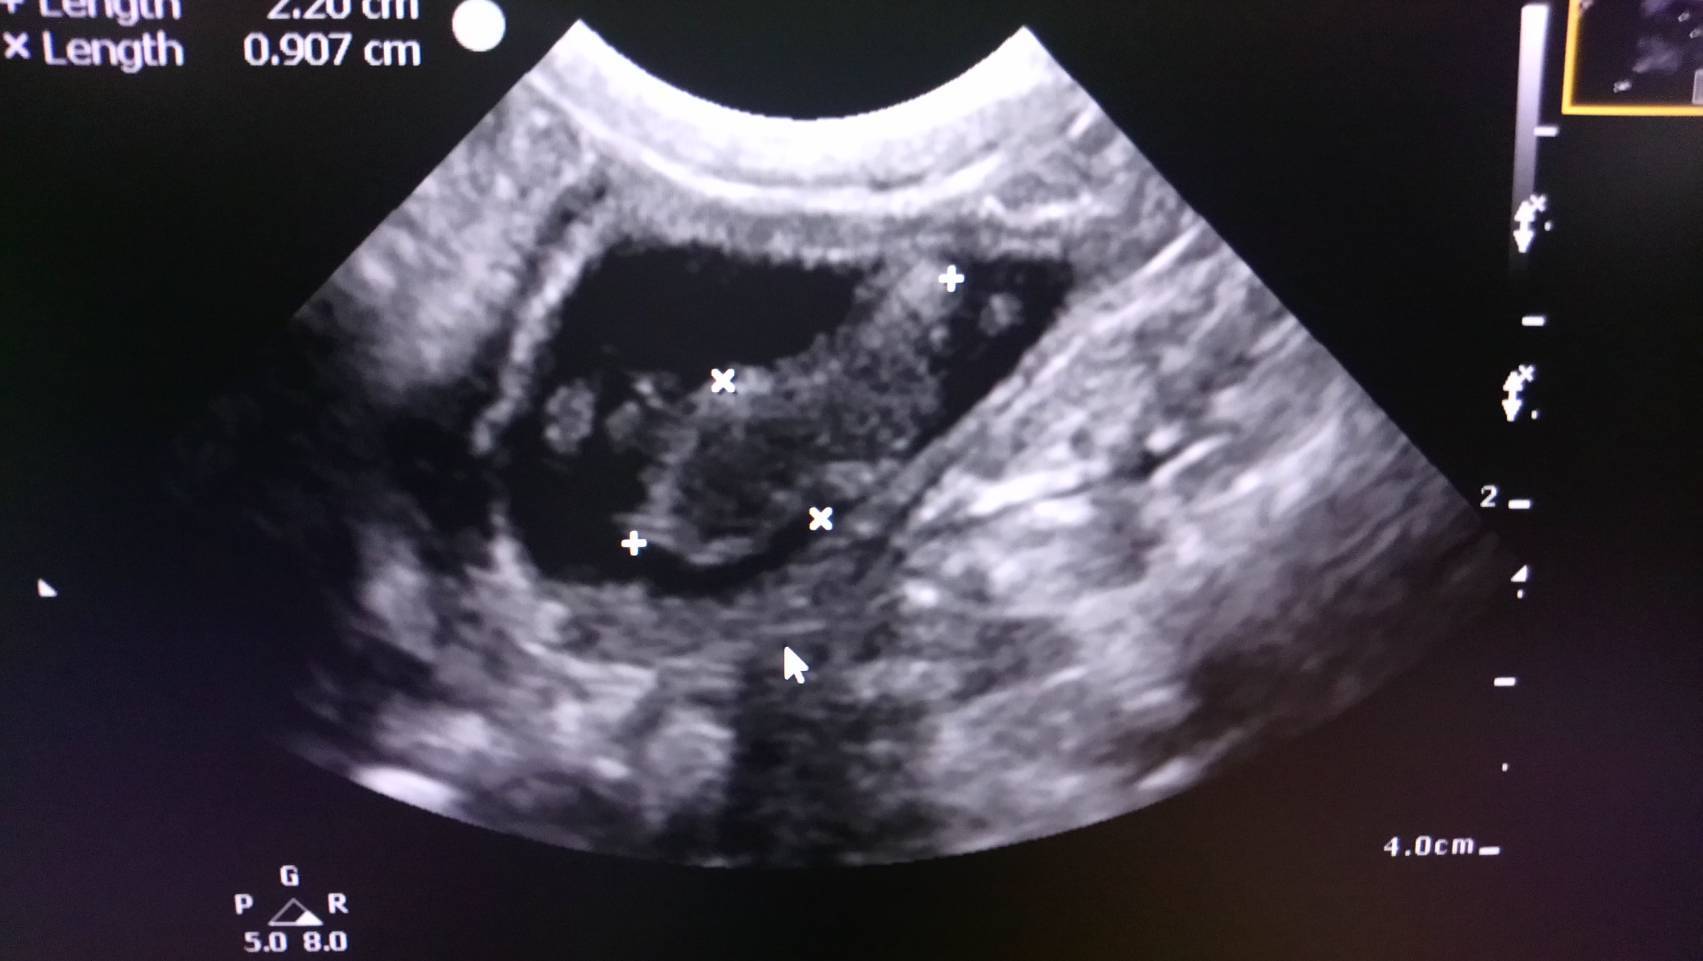

主題: 車禍重傷的小枳第三階段醫療費用 申請者姓名: 王昀 花色: 申請日期: 2018-03-04 05:51:39 申請者部落格: 申請者臉書網址: https://www.facebook.com/Wangyunpet 所在縣市/合作醫院: 台北市/澄諾動物醫院 治療費用: 18153元 需求人數: 39人 已結案 (2024-06-01 13:15:03) 報名人員: 小貍仔(已付款)、MinCat(已付款)、Yvonne(已付款)、薇薇安(已付款)、Tracy Hsu x2(已付款)、Meditator(已付款)、灰色貓(已付款)、Elsa Tu(已付款)、Wenny Chen(已付款)、Eve(已付款)、洪凱威 x2(已付款)、小康(已付款)、Nina(已付款)、碰碰(已付款)、Shu-Han Pan(已付款)、jill(已付款)、miraai x2(已付款)、Sophia x10(已付款)、Sophia x9(已付款)、 候補人員: 動物病情說明: 遭遇車禍受重傷的小枳經過疝氣手術保住性命後,接著在專業的骨科醫院進行股骨頭切除手術後,主治醫師顧慮貓咪對陌生環境較為敏感的個性,所以術後將小枳帶回原醫療院所休養,預計手術傷口復原期為14天,但在傷口復原期間,主治醫師發現小枳的尿液帶有黑褐色的碎屑,於是為小枳進行超音波檢查,檢查結果發現小枳的膀胱有幾個血塊,因此主治醫師在照顧小枳手術傷口的同時也為小枳進行膀胱血塊的清除。

膀胱血塊的清除是漸進、緩慢的工作,不是一時半刻可以見效的,除了投藥之外,更重要的是補充足夠的水分以增加小枳的排尿量,讓血塊隨著尿液排出體外,主治醫師利用各種方式增加小枳的喝水量,比如在罐頭裡加水、給予泥狀的食物等等。小枳在醫生的悉心照顧下,排尿量增加,膀胱血塊逐漸縮小。小枳原本14天的休養期也因此拉長到25天,在小枳膀胱血塊削減到大約只剩下百分之十時,因為膀胱血塊的消除沒有一定的時間,醫生也無法斷言膀胱血塊完全消除需要多久的時間,因此決定讓小枳出院,但醫生有叮囑我要注意觀察小枳排尿情況,如小枳排尿量減少或尿液中帶有黑褐色碎屑要立即帶小枳回診。